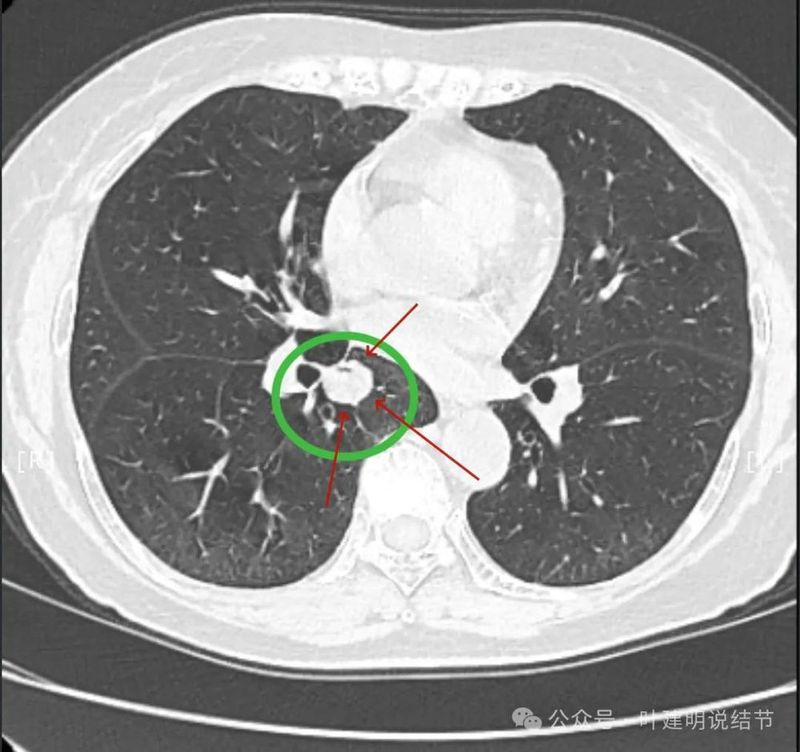

先看患者提供的2024年2月份的CT影像:

病灶出现,在右下叶支气管旁边,轮廓清楚,此层似磨玻璃密度。

表面似分叶状,密度不纯,邻近血管略有弯曲向病灶。

上图这个层面感觉病灶与肺血管之间没有明显间隙,似像侵犯或愈着的样子。